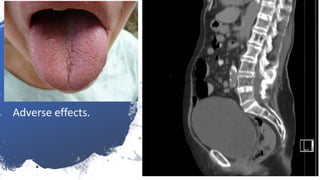

Beta 2

Agonists

Adverse

effects.

Sinus

tachycardia

tremors

Anti

muscarinic

Adverse effects.